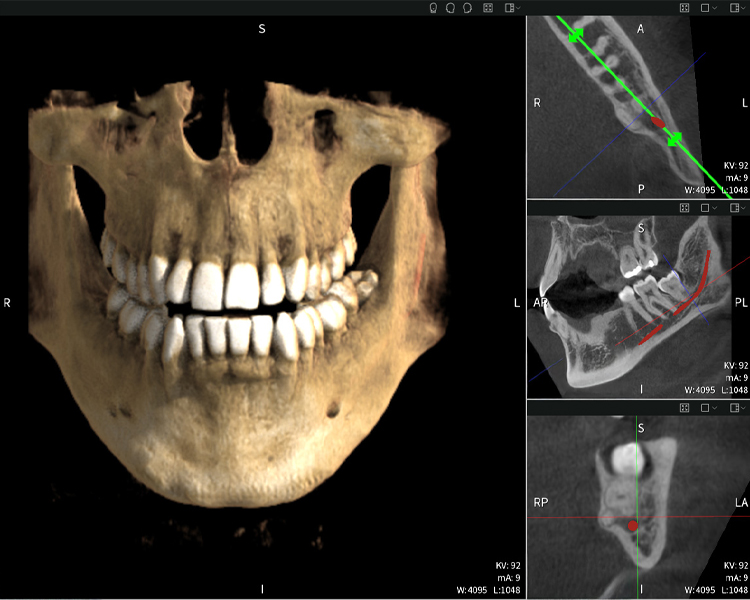

Abbildung a

- Oben links: Axiale Schnittansicht des linken Unterkiefers (Region 38) mit Darstellung des Nervus alveolaris inferior (rot) in unmittelbarer Nähe zu den Wurzeln des Zahns 38.

- Oben rechts: 3D-Rekonstruktion des gesamten Unterkiefers zur Orientierung. Der rot markierte Nervus alveolaris inferior verdeutlicht seine Lage im Kieferknochen.

- Unten links: Sagittale Ansicht des Unterkiefers (Region 38), die die enge räumliche Beziehung zwischen den Wurzeln und dem Nervenkanal verdeutlicht.

- Unten rechts: Koronale Ansicht des Unterkiefers (Region 38) entscheidend für die Beurteilung der räumlichen Lage der Wurzeln zum Nerven.

Abbildungen b–d zeigen verschiedene Ansichten einer 3D-Rekonstruktion des Unterkiefers und bieten eine umfassende Übersicht über die Anatomie des Unterkiefers, die Lage der Nerven im Verhältnis zu den Zähnen und ermöglichen die Beurteilung der Zahnsymmetrie und Ausrichtung.

Abbildung d zeigt den bereits vorbehandelte Zahn 48, dessen Krone entfernt wurde und dessen Wurzeln nahe am Nerv belassen wurden, was das hohe Risiko einer Nervenschädigung verdeutlicht.